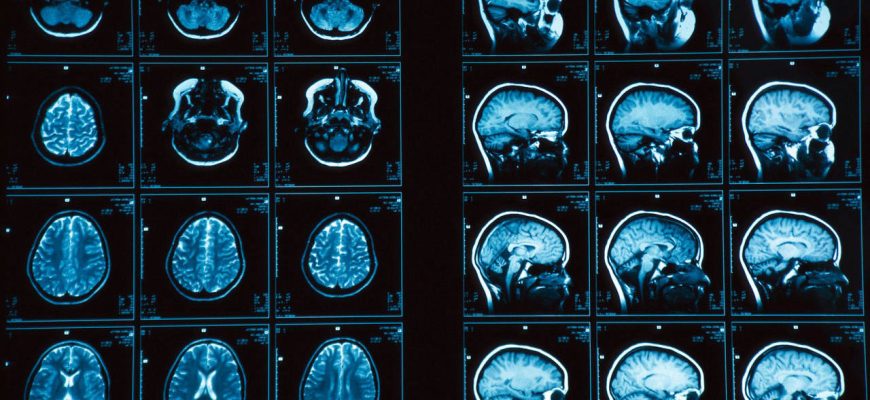

Искусственный Интеллект на Страже Здоровья: Как Мы Разработали ИИ для Анализа МРТ Снимков Мозга В эпоху стремительного развития технологий искусственного

Как Искусственный Интеллект Спасает Жизни: Наш Опыт Разработки ИИ для Анализа МРТ Привет, друзья! Сегодня мы хотим поделиться с вами захватывающей историей